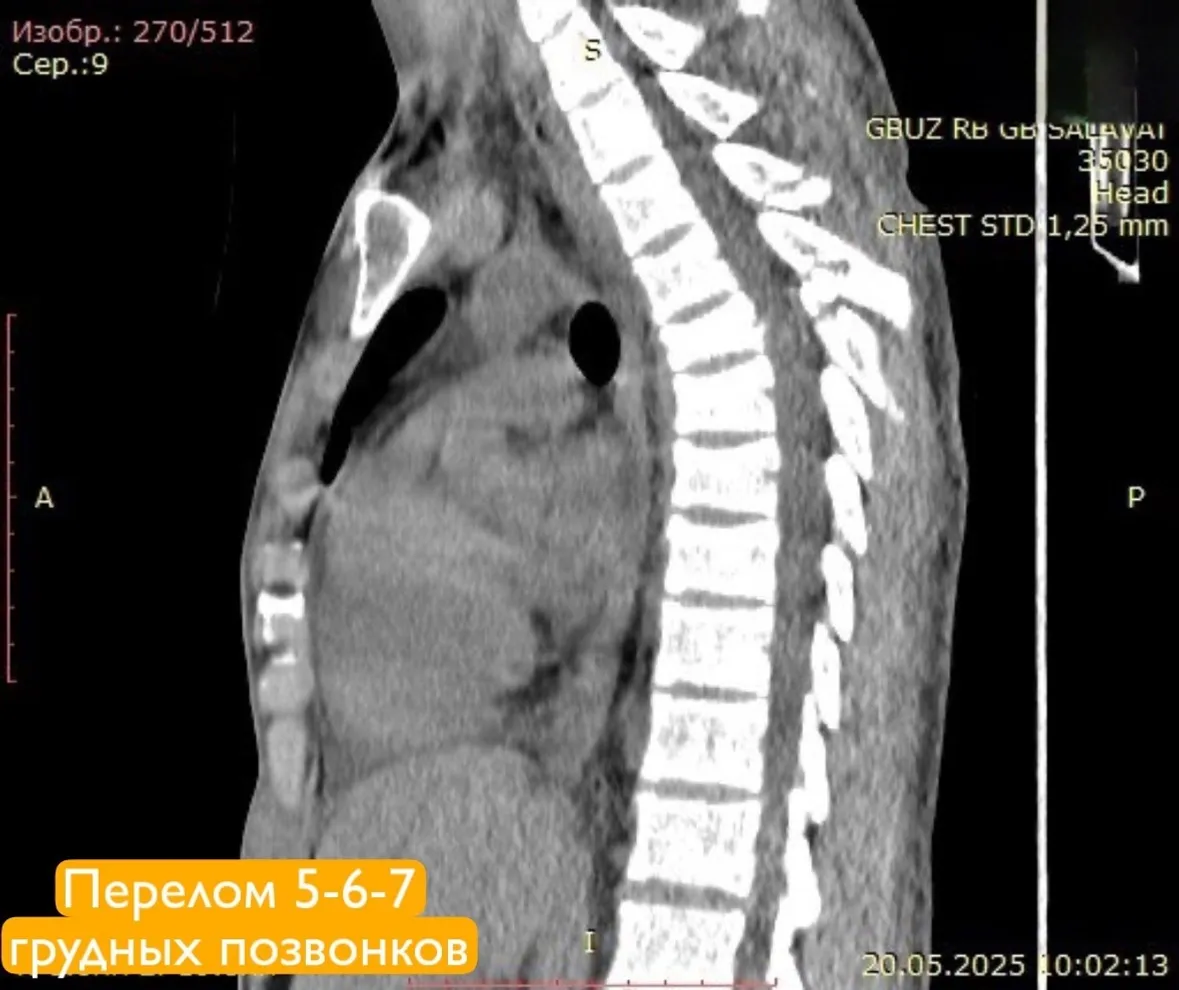

У пациента диагностировали сочетанную травму: ушиб головного мозга, переломы шейных и грудных позвонков, а также ребер и ушиб легких. Особенно серьезной была ситуация с переломами 1 и 2 шейных позвонков со смещением. Травма могла привести к острому сдавлению спинного мозга и угрожать жизни молодого человека. Такие переломы часто приводят к инвалидизации, вплоть до полного обездвиживания.